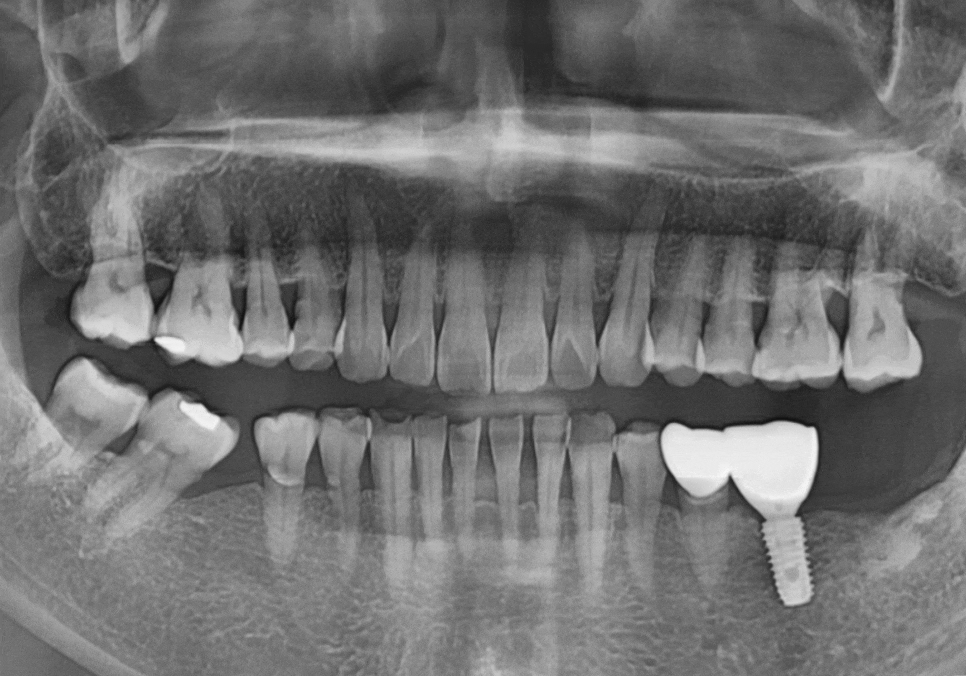

왼쪽 어금니 치료 과정

발치 후 빈 공간, 이 빼고 오래 냅두면 이렇게 됩니다.

왼쪽 어금니는 맨 끝 치아가 상실된 상태라,

임플란트를 진행하기로 했습니다.

하지만 위쪽 치아가 아래로 내려온 탓에,

임플란트 머리(보철물)가

들어갈 높이가 너무 낮았는데요~

이대로 머리를 올리면 보철물이

자꾸 빠지는 부작용이 생길 수 있어요.

이럴 경우, 정출된 윗 치아를 다듬어서

#37 임플란트 머리가 들어갈 공간을

확보해야 합니다.

저희는 단순하게 치아를 다듬는 과정도

눈대중으로 대~강 하지 않습니다.

구강스캐너로 정밀 데이터를 얻어

3D 분석을 먼저 진행한 뒤,

어느 부위를 얼마나 다듬어야

최적의 공간이 나올지 미리 시뮬레이션합니다.

그래야 자연치아에 큰 손상이 가지 않는

최소한의 범위 내에서만

정교하게 다듬을 수가 있거든요~

덕분에 치아 손상은 최소화하면서,

임플란트 보철물은 아주 안정적인 높이로

올라갈 수 있었습니다. ^^

230420 /240808